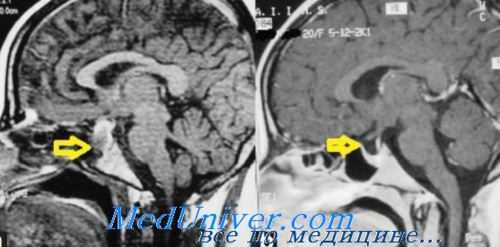

- Рентгенологические и томографические исследования. В ходе рентгенографии черепа, КТ турецкого седла, МРТ головного мозга и гипофиза могут визуализироваться опухоли, кровоизлияния, водянка, увеличение размеров и деформация турецкого седла.

Диагноз устанавливается клинически, анамнестически и лабораторно (в первую очередь исследуется гормональная формула крови и уровень гонадотропных гормонов в моче, различные параметры метаболизма и т.п.). Разработаны подробные критерии дифференциальной диагностики от заболеваний со сходной симптоматикой (болезнь Иценко-Кушинга, гиперкортицизм, гипотиреоз, первичный гипогонадизм и т.д.). Инструментальные исследования назначаются с целью обнаружения органической патологии в эндокринных мозговых структурах (КТ, МРТ, рентгенография).